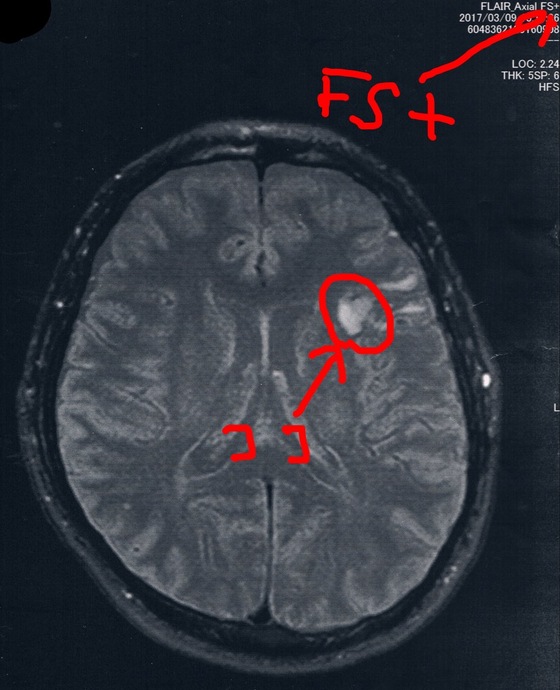

前回2016/9/8(手術後27か月)のMRI画像

前回と今回の画像で撮り方が違うらしくて白黒が違うのだけど、毎回おんなじMRI設備で同じ撮影方法で検査して欲しいなぁ。。。